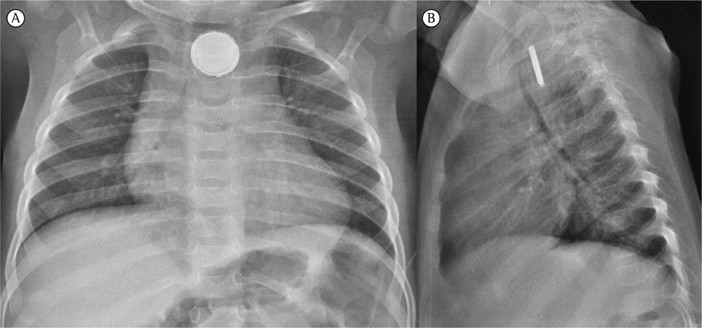

È finalmente fuori pericolo il bambino di 17 mesi arrivato al Pronto Soccorso dell’Ospedale G. Gaslini nella notte di sabato 14 maggio, dalla provincia Savona per "vomito con sangue ed anemia”. I genitori hanno raccontato ai medici che da una settimana non stava bene, non voleva mangiare ed aveva febbricola. Il chirurgo di Pronto Soccorso, dott. Vittorio Guerriero lo aveva immediatamente sottoposto a radiografia, rilevando un immediato pericolo di vita: si trattava di una pila al litio localizzata nell'esofago del bambino, che aveva determinato vomiti di sangue e progressiva anemizzazione da necrosi colliquativa (il meccanismo di danno dell'esofago) e conseguente ulcerazione del viscere.

“Nella notte del 14 maggio è stata attivata immediatamente la task force che comprende: radiologo, chirurgo toracico, cardiochirurgo, endoscopista digestivo, endoscopista respiratorio, strumentiste, perfusioniste, anestesisti e rianimatori. Al bambino è stata praticata, dopo pochi minuti dall'acceso in PS, un’intubazione dal dott. Andrea Dato e dalla dott.ssa Lara Petrucci, quindi si è proceduto con l'apertura del torace ad opera del cardiochirurgo Francesco Santoro e del chirurgo toracico Michele Torre, i quali hanno messo in sicurezza i grandi vasi dall'esofago danneggiato; quindi sono intervenuti gli endoscopisti digestivi - dott. Paolo Gandullia e dott.ssa Serena Arrigo - che hanno avuto difficoltà a localizzare la pila perchè il tessuto era necrotico, si sfaldava e sanguinava; la pila inoltre aveva scavato con il tempo una nicchia. Dopo la rimozione del tessuto che la copriva, è stata rimossa per via endoscopica. Quindi l'endoscopista respiratorio, dott. ssa Annalisa Gallizia, ha esaminato la trachea per escludere un potenziale danno alle vie respiratorie. Dopo circa due ore si è concluso l’intervento” spiega Raffaele Spiazzi, Direttore Sanitario dell’ospedale Gaslini.